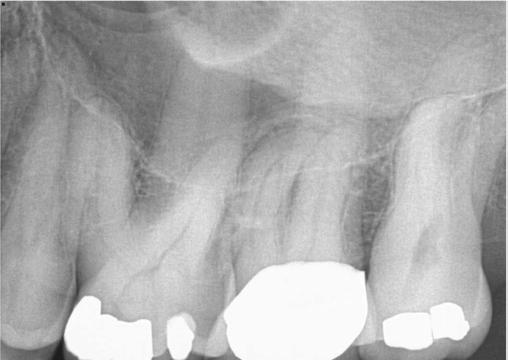

A 59-year-old male reported to the dental office with missing maxillary teeth due to poor oral hygiene. Treatment planning was done for all on four implant placements followed by prosthesis. A complete medical history was obtained and was negative for any significant medical problems. The patient denied being allergic to any medication as well. The patient agreed to the implant placement and was advised to have an orthopantomogram (Figure 1).

Figure 1: Pre-op panoramic radiograph Figure 2 (left): Alveolar antral artery (AAA). Figure 3 (center): The artery has been ligated with suture. Figures 4A and 4B (right): CBCT post-implant placement and position of the artery coronally (top). 4B. Showing the position of alveolar antral artery (AAA) in relation to implant placement as indicated by the yellow arrows (bottom)

Figure 5: Panoramic radiograph following implant placement